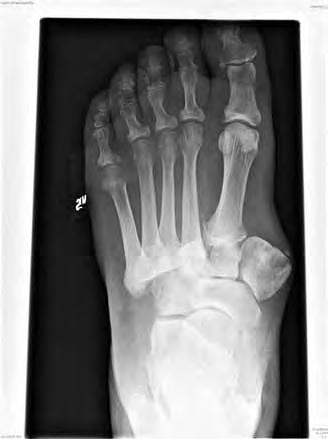

vänster med kraftig abduktionsfelställning. indikation för korrigerande osteotomi i sårfritt intervall.

Typ II Mellanfot med TMT-leder (Figur 1)

Mellanfotscharcot leder vanligen till massiv bennybildning. Framfoten kan gå i kraftig abduktion med beniga prominenser medialt liksom nedsjunket eller reverserat fotvalv.